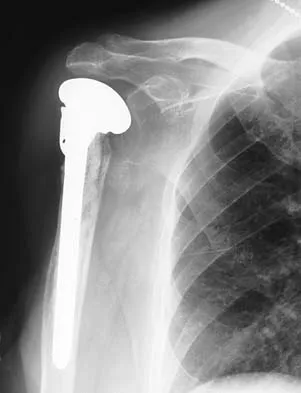

Which of the following findings is seen in the chest radiograph shown in Figure 13?

Orthopaedic surgeons are often responsible for interpreting radiographs of general examinations such as the chest radiograph shown. For accurate interpretation, it is important to systematically review all of the information available on the radiograph. Using this approach, the fracture of the left proximal humerus is readily recognized. Linear air soft-tissue density at the lung periphery would suggest a pneumothorax, but this finding is not shown on the radiograph. The upper thoracic spine is well aligned. The sternoclavicular and distal clavicles are normal.